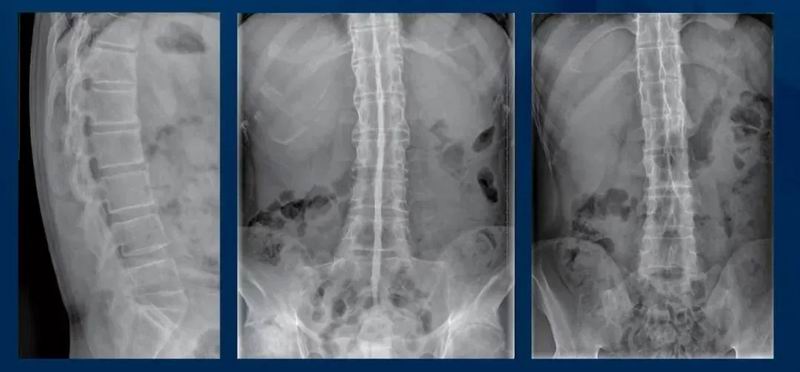

强直性脊柱炎的腰背痛有何特点

强直性脊柱炎是一种主要累及脊柱和骶髂关节的自身免疫性炎症性疾病,随着疾病的进展,逐渐出现脊柱和关节的强直及功能障碍。

腰背痛特点

直性脊柱炎所致的炎性腰背痛(有别于机械性腰背痛,2009年ASAS炎性腰背痛标准:

①发病年龄<40岁。

②隐匿起病。

③活动后改善。

④休息不能缓解。

⑤夜间痛。

满足≥4项可判断其存在IBP。